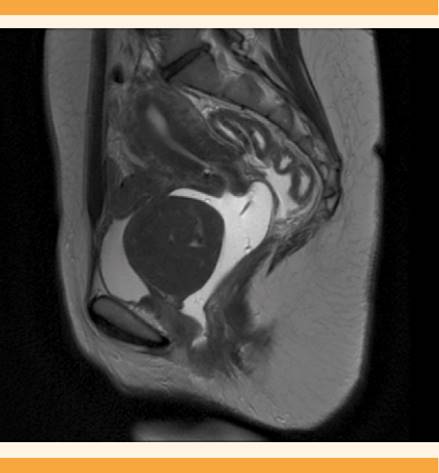

Después de algunos meses acudió, nuevamente, a consulta médica, indicando un incremento significativo de los síntomas, entre los que destacaron importantes molestias vaginales, metrorragias mayores al ciclo menstrual y dispareunia, por lo que se decidió repetir el estudio ecográfico (Figura 1y2) y complementarlo con resonancia magnética para mayor definición. La tumoración aumentó notoriamente de tamaño (58 x 57 x 60 mm), con forma redondeada y aspecto sólido, zonas de hiperseñal en su espesor, quizá por la coexistencia de estructuras venosas y áreas de degeneración mixoide. No se identificaron otros cambios que sugirieran malignidad. La tumoración se encontraba en el espacio vesicovaginal, al parecer dependiente de la pared anterior vaginal, aislada del cuello uterino y del útero, pero sugerente de compresión de la pared posterior de la vejiga urinaria (Figura 3). Con estos datos se estableció el diagnóstico de leiomioma vaginal pediculado. Debido a los signos y síntomas se inició el tratamiento con acetato de ulipristal (5 mg al día) para disminuir el volumen y sangrado miomatoso. Después de dos ciclos de tratamiento la tumoración se incrementó a 70 x 55 mm, por lo que se solicitó la participación multidisciplinaria del servicio de Urología y en común acuerdo se decidió la miomectomía por vía vaginal, esta vez con consentimiento de la paciente.

Figura 3 Resonancia magnética que evidencia una tumoración en el espacio vesicovaginal, dependiente de la cara vaginal anterior, que comprime la pared posterior vesical.